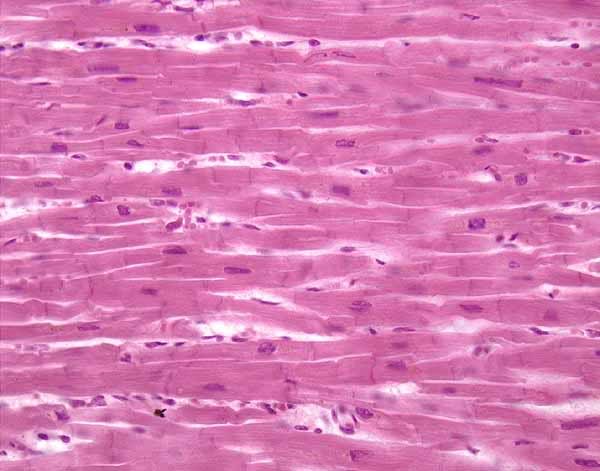

Cardiac Muscle Intercalated discs

More Cardiac Muscles

muscle cardiac intercalated